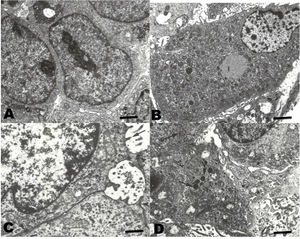

In TEM (Figure 5), the neoplastic cells of conventional HCC resembling the normal liver cells. Abundant endoplasmic reticulum and mitochondria were observed. These cells showed aggregates of glycogen in the cytoplasm. Occasionally, clear cells with abundant lipid vacuoles were observed. In the sarcomatoid HCC, spindle cells with numerous osmophilic granules were observed. In addition, mucin-like vacuoles were observed. Isolated narrow cell junctions and microvillus-like prolongations were observed.

The ultra-structural characteristics of conventional HCC have been widely described for both human and other mammalian HCC (Lapis 1988; Grab, Skubleny, and Kneteman 2019). The cells contain abundant rough endoplasmic reticulum, a relevant number of mitochondria, and glycogen and lipid vacuoles. These utrastructural characteristics are similar to those found in normal hepatocytes (Baratta et al. 2009). On the other hand, sarcomatoid HCC, also called fibrolamellar, has presented cells which are very different from those of normal hepatocytes; being spindle-shaped, with electrodense granules, and with narrow cell junctions (Andreola, Audisio, and Lombardi 1986; Hasegawa 1996). In all the cases reviewed in this work, they showed an ultrastructure similar to those described in the literature for HCC in mammals and humans.

In this work, the detailed recognition of the tissue and cellular structure of the neoplasms proved an important tool for diagnosis in addition to immunohistochemistry. Although electron microscopy provided a less-specific methodology for the objectives of the study, the ultrastructural findings were as expected and were useful to support the histopathological diagnosis.